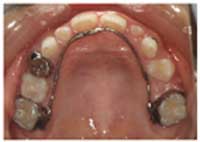

この治療はリンガルアーチという装置で行っています。細い針金で動かした後、歯が後ろに戻らないように、止めています。